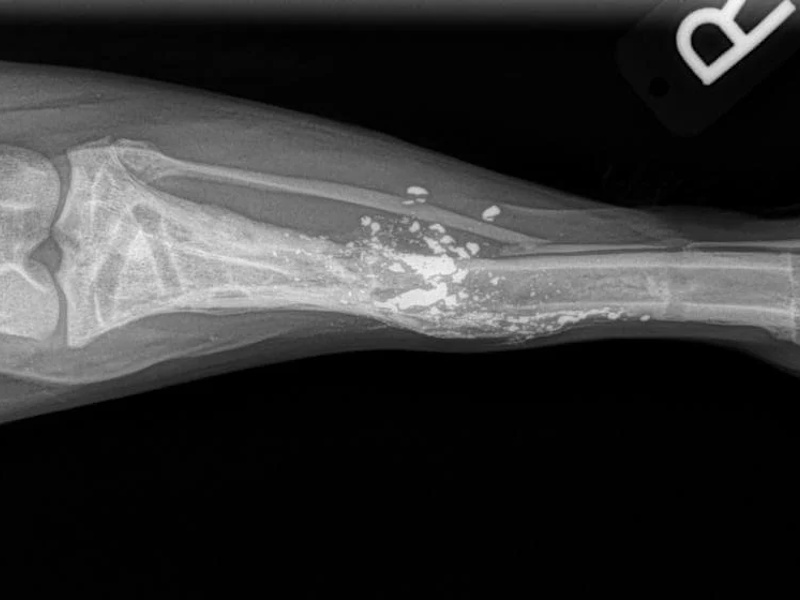

Types of Fractures

Fore Limb (Humerus, Radius/Ulnar, Metacarpus)

Hind Limb (Pelvis, Femur, Patella, Tibia/Fibula, Lateral Malleolus)

- Fracture Fixation: $4,000 - $8,000+